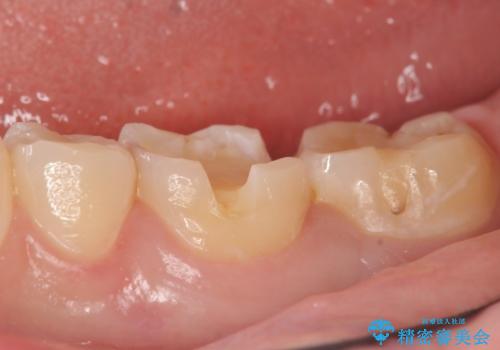

- 冷たいものを飲むと、左下奥歯がしみると来院された方の症例です。

検査の結果左下6が虫歯になっていたため、セラミックインレーによる修復を行いました。

当院のセラミックインレーはemaxという強度と審美性に優れた材料を使用しています。

またプレス方式でインレーを製作しているため、削り出しで製作するCADCAMより優れた適合性も持ち合わせており、虫歯が再発しにくい修復物です。